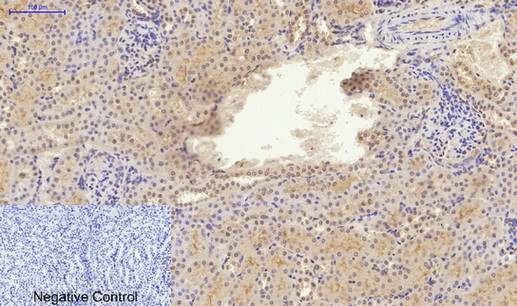

ARG66190 anti-Smad 2 antibody IHC-P image

Immunohistochemistry: Paraffin-embedded Rat kidney tissue stained with ARG66190 anti-Smad 2 antibody at 1:200 dilution (4°C, overnight). Antigen Retrieval: Boil tissue section in Sodium citrate buffer (pH 6.0) for 20 min.

Negative control was used by secondary antibody only.